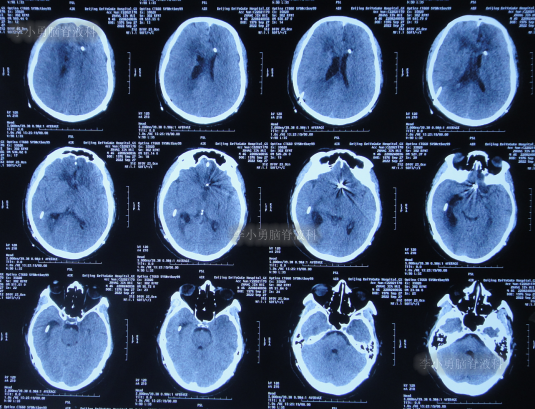

2022年9月14日(住院治疗21天),体温变正常,查头颅CT示双侧脑室均变小(图-17)。

图-17:2022年9月14日头颅CT

2022年9月27日(住院治疗34天),患者出现意识差,查头颅CT示颞角扩张(图-18)。

图-18:2022年9月27日头颅CT

2022年10月12日(住院治疗49天),脑脊液真菌彻底消灭,查头颅CT示颞角缩小(图-20)。

图-20:2022年10月12日头颅CT

脑脊液各项化验均正常后于2022年12月14日(住院治疗112天),进行了脑室腹腔分流术(图-23)。

图-23:2022年12月14日头颅CT

2022年12月27日(李小勇脑脊液科治疗125天)康复出院,出院时:神清气爽,心情愉悦,走路基本正常,言语交流正常(图-24);出院时头颅CT示未见异常(图-25)。

图-25:出院时头颅CT